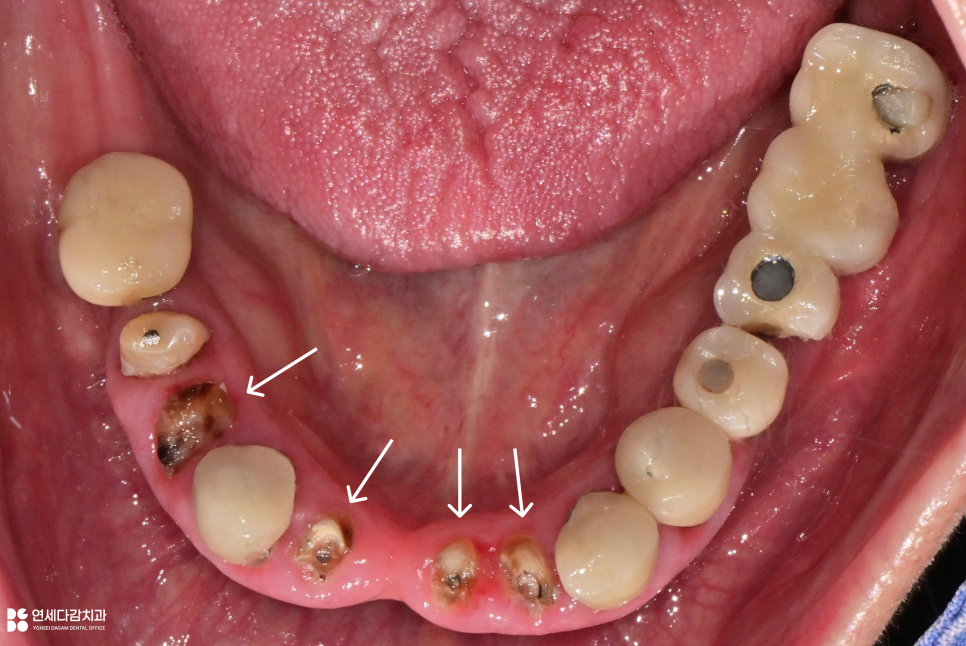

먼저 술전 사진을 확인해 보면,

아랫니들은 충치로 파절이 되어 있습니다.

치관은 이미 손상되어 남지 않았으며,

치아 뿌리만 확인되는 부위도 있습니다.

이렇게 치관이 없고 치근만 남은 경우를

잔존 치근이라고 부릅니다.

치관이 없으니 기능을 할 수 없고,

잇몸 아래 남아 있는 잔존 치근들은

염증과 감염의 원인이 될 수 있어

발치는 불가피한 상황입니다.